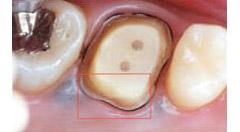

右の写真をご覧ください。

歯を歯茎近くまで削らなくてはならないほど進行した虫歯の写真です。通常なら抜歯後にインプラントや入れ歯で治療することになります。

エクストリュージョン法を用いれば、このような状態でも治療できます。

残った歯を歯茎の上まで引っ張り上げ、被せ物の土台にすることで抜歯を回避するのです。